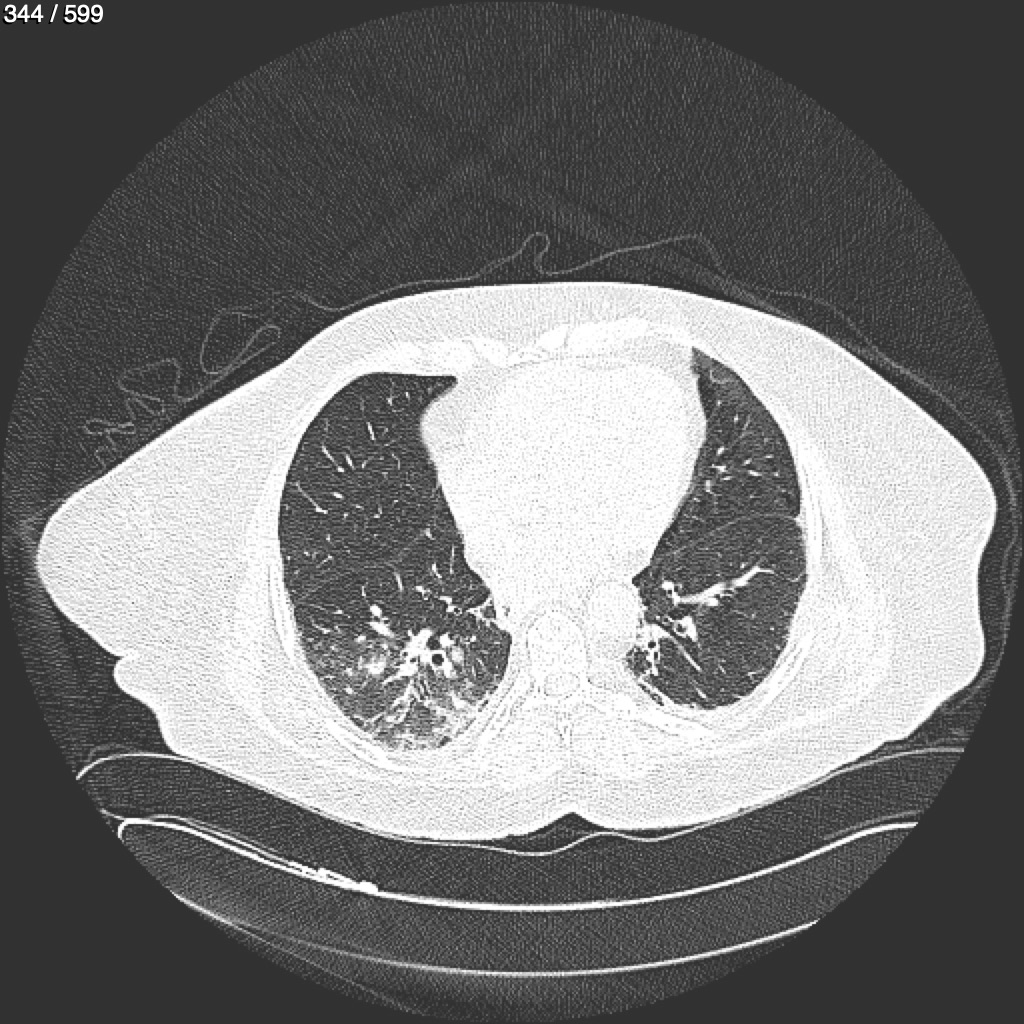

Home G​l​o​r​i​a​ ​G​l​a​d​y​s​ ​B​e​a​s​l​e​y​ ​-​ ​T​ó​r​a​x​ ​T​o​r​a​x​_​S​i​m​p​l​e​ ​(​A​d​u​l​t​o​)